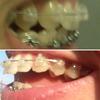

Схема чейна - от брекета на клыке слева до брекета на клыке справа, натянут под брекетами. Я уже год назад так носила.

Наклон на ВЧ сильный...

На верхнем фото - наклон в год ношения БС, на нижнем - сейчас.